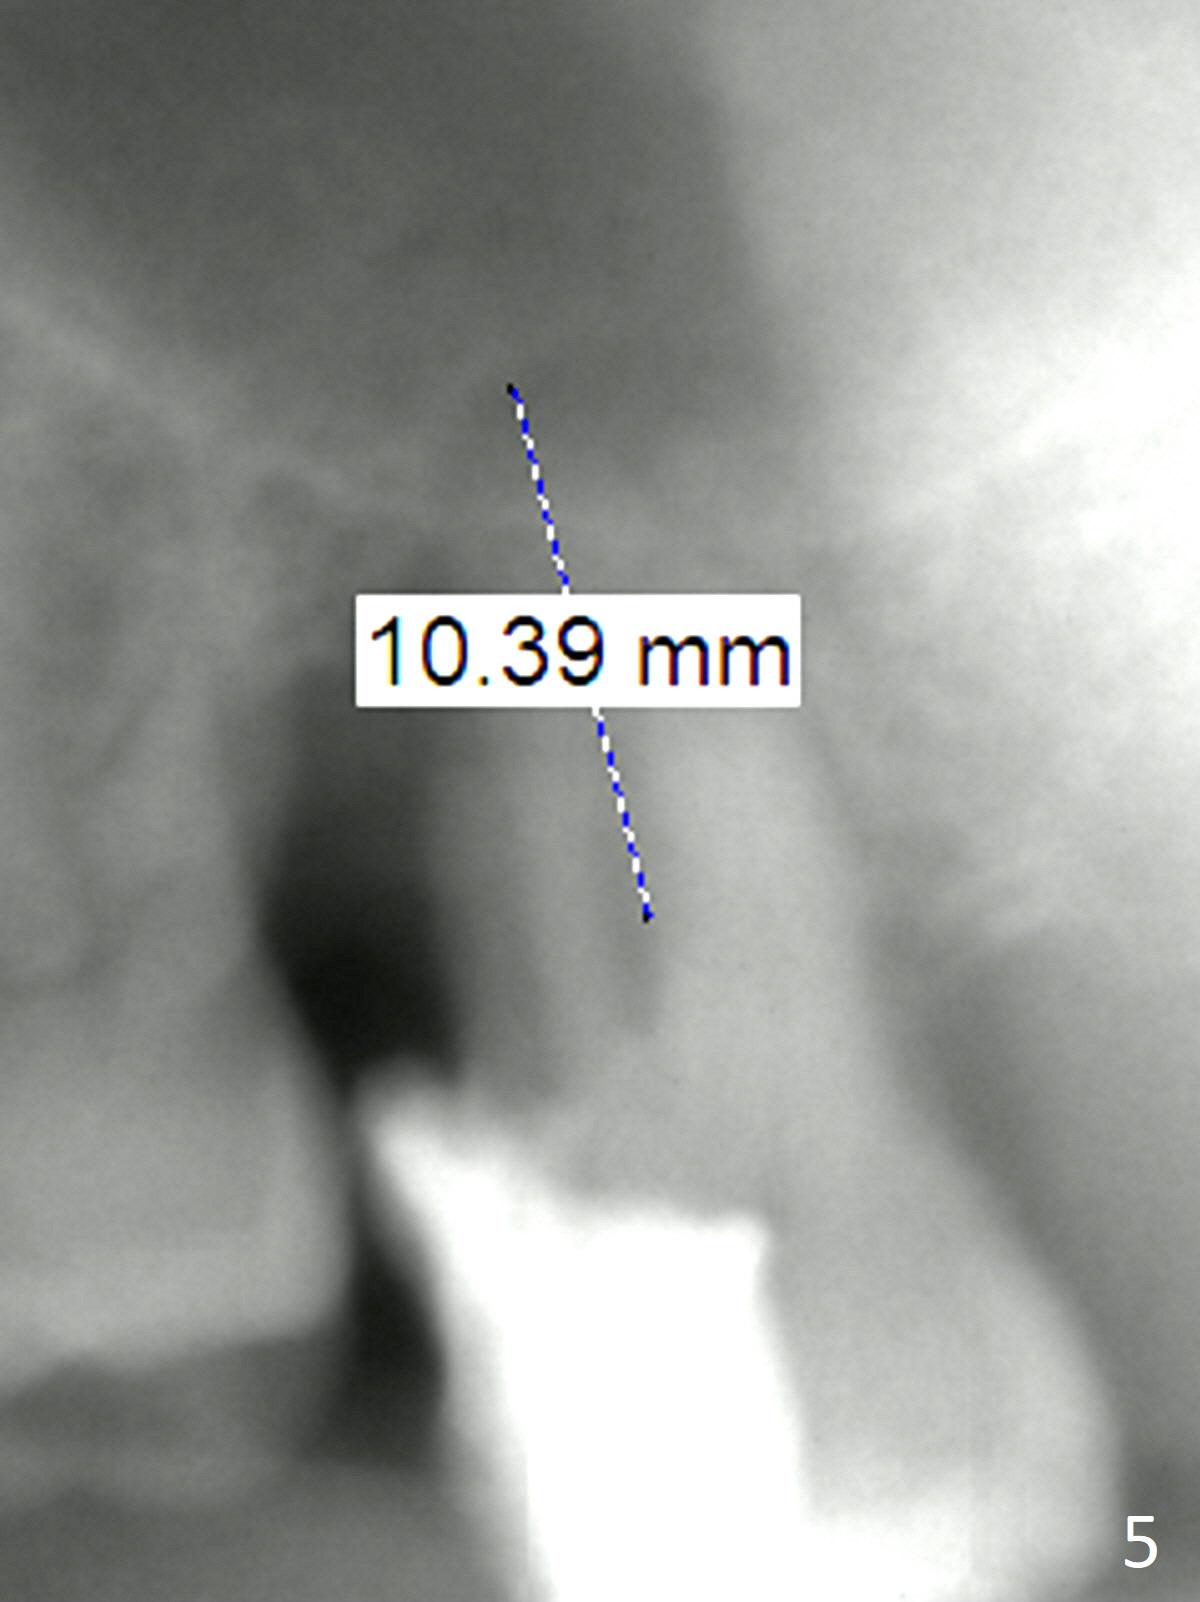

Bone loss seems to be the most severe around the mesiobuccal root (Fig.2 *), from which the osteotomy should stay away (Fig.3). It may be the safest to place an implant in the palatal socket, leaned as buccally as possible so that the coronal end of the implant will be in the center of the extraction socket. Re-measure the palatal socket length from PA and Pan: 8.5 and 10 mm, respectively. The implant length should be around 10 mm. Place bone graft before the final tap and take X-ray.